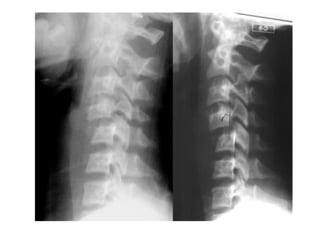

• Investigations

– Confirmatory

• Xrays

• CT

• MRI

• Myelography